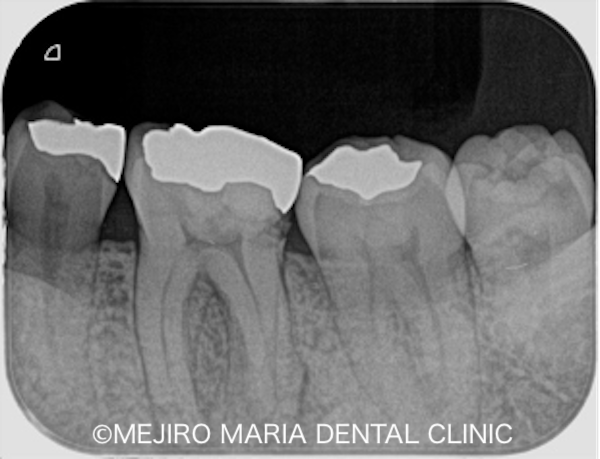

根管治療は2回で終了し、2回目の治療では長年歯茎に見られていたフィステル(瘻孔)も消失していました。症状の消失が確認できたため最終補綴処置に移行しました。今後3ヶ月間〜2年間の経過観察を行い、引き続きフォローアップする予定です。

今回の症例は、長年、歯茎が腫れることに気付いてはいたものの、痛みや日常の違和感がさほどないことから放置してしまった症例です。今回のように1回の治療で歯茎の腫れが消失し、無事に終わるとは限りません。歯周組織への炎症の波及が大きいとダメージも広がり、難治化する場合も多くあります。

初回の根管治療を正しい方法(コンセプトを守った処置)にて行うことで、再発のリスクは最小限に抑えられます。また、予後不良の場合は歯根端切除術が必要なケースもありますが、結果的に、将来的な再根管治療を回避することで歯の強度を守ることにつながります。